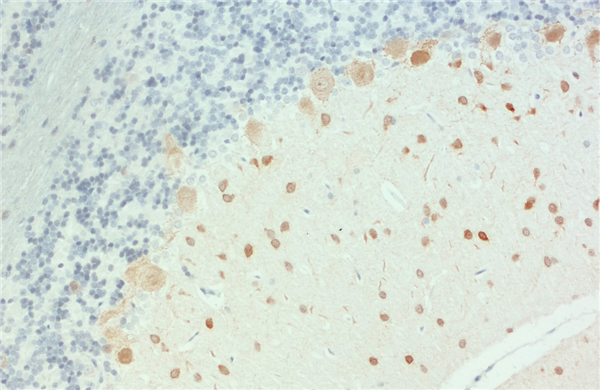

免疫組化(石蠟切片)(IHC-P):使用雞抗帕爾瓦林抗體(產(chǎn)品編號 195 009,稀釋度 1:4000,DAB 染色,棕色)對甲醛固定的石蠟包埋大鼠小腦切片進行間接免疫染色。細胞核通過蘇木精染色顯示(藍色)。